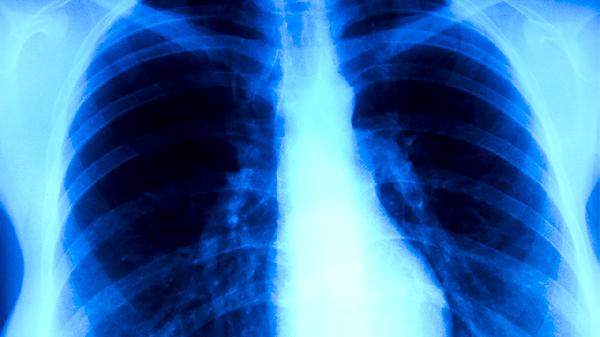

肺积水的严重性需根据具体病因和病情进展判断,轻度肺积水可能无明显症状,但重度肺积水可能导致呼吸困难甚至危及生命。肺积水通常由心力衰竭、肺部感染、肾功能不全等疾病引起。

轻度肺积水患者可能仅表现为活动后气短或轻微咳嗽,此时通过治疗原发病、限制钠盐摄入等措施可有效控制病情。若积水未及时处理,可能逐渐加重并影响肺功能,患者可能出现平卧时呼吸困难、夜间阵发性呼吸困难等症状。部分患者因胸腔积液压迫肺部组织,出现持续性低氧血症,需通过氧疗或胸腔穿刺引流缓解症状。

重度肺积水常见于急性左心衰竭、严重肺炎或恶性肿瘤胸腔转移等疾病,患者可能出现端坐呼吸、咳粉红色泡沫痰、意识模糊等危急表现,需紧急医疗干预。若合并多器官功能衰竭,病死率较高。少数情况下,肺积水进展迅速且对常规治疗反应差,如急性呼吸窘迫综合征或脓胸,需机械通气或手术治疗。